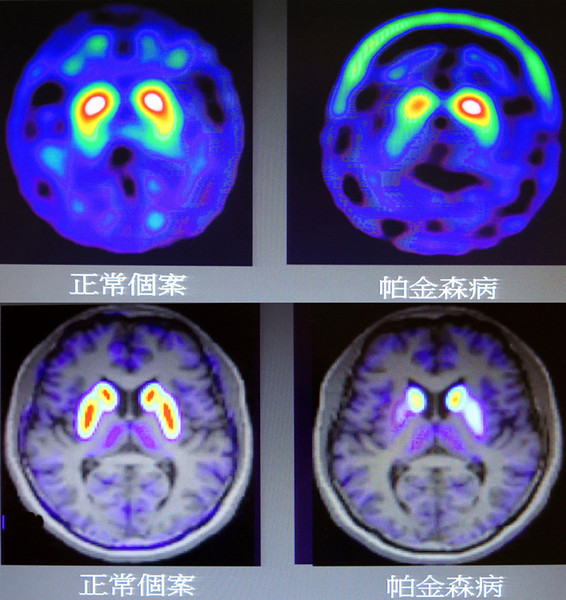

現階段臨床上缺乏早期診斷帕金森氏症的有效技術,閻紫宸指出,包括抽血、腦部電腦斷層或磁振造影,對疾病診斷並無幫助;長庚核子醫學科主任林昆儒解釋,中腦部位的黑質細胞數量並不多,就算「全部死光」,該部位的神經結構仍無明顯變化,使電腦斷層及磁振造影等技術,無從分析疾病與正常腦部的差異。

長庚神經科學中心主任陸清松表示,治療帕金森氏症的另一困境,是難以具體描述病程的變化,多採「症狀量表」來追蹤療效,未盡客觀及精準;閻紫宸分析,目前臨床上使用的「鎝99m-多巴胺轉運體分子造影」雖可協助診斷,但影像品質及偵測範圍都受限制,而長庚5年前開始研發的AV133正子影像技術則已突破侷限,能精準區隔正常老化及帕金森氏症,相關研究兩度登上《核子醫學期刊》。

林昆儒指出,AV133是一種放射性追蹤劑,由於分子小、又為「親脂性」,透過靜脈注射進入人體後,可通過「血腦障壁」深入大腦,並進入與多巴胺、血清素及正腎上腺素等3種物質有關的神經細胞內部,與「囊泡轉運體VMAT2」結合,而VMAT2又與多巴胺相連,因此當黑質細胞減少分泌多巴胺時,與VMAT2結合降低,AV133顯示的放射性訊號就會減弱,即可據此評估帕金森氏症嚴重的程度。

「AV133系統可分辨早期帕金森氏症,並區別疾病嚴重程度,」閻紫宸表示,該技術可直接「定量」影像數據,作為評估藥效、預後及病程的基準;長庚腦神經內科副教授翁意欣說明,典型帕金森氏症與「進行性核上眼神經麻痺症」、「皮脂基底核退化症」,或部分中毒、中風引發之續發性症候群的初期症狀相似,治療方法卻大相逕庭,未來可望藉由AV133正子影像技術,進行正確的診療。